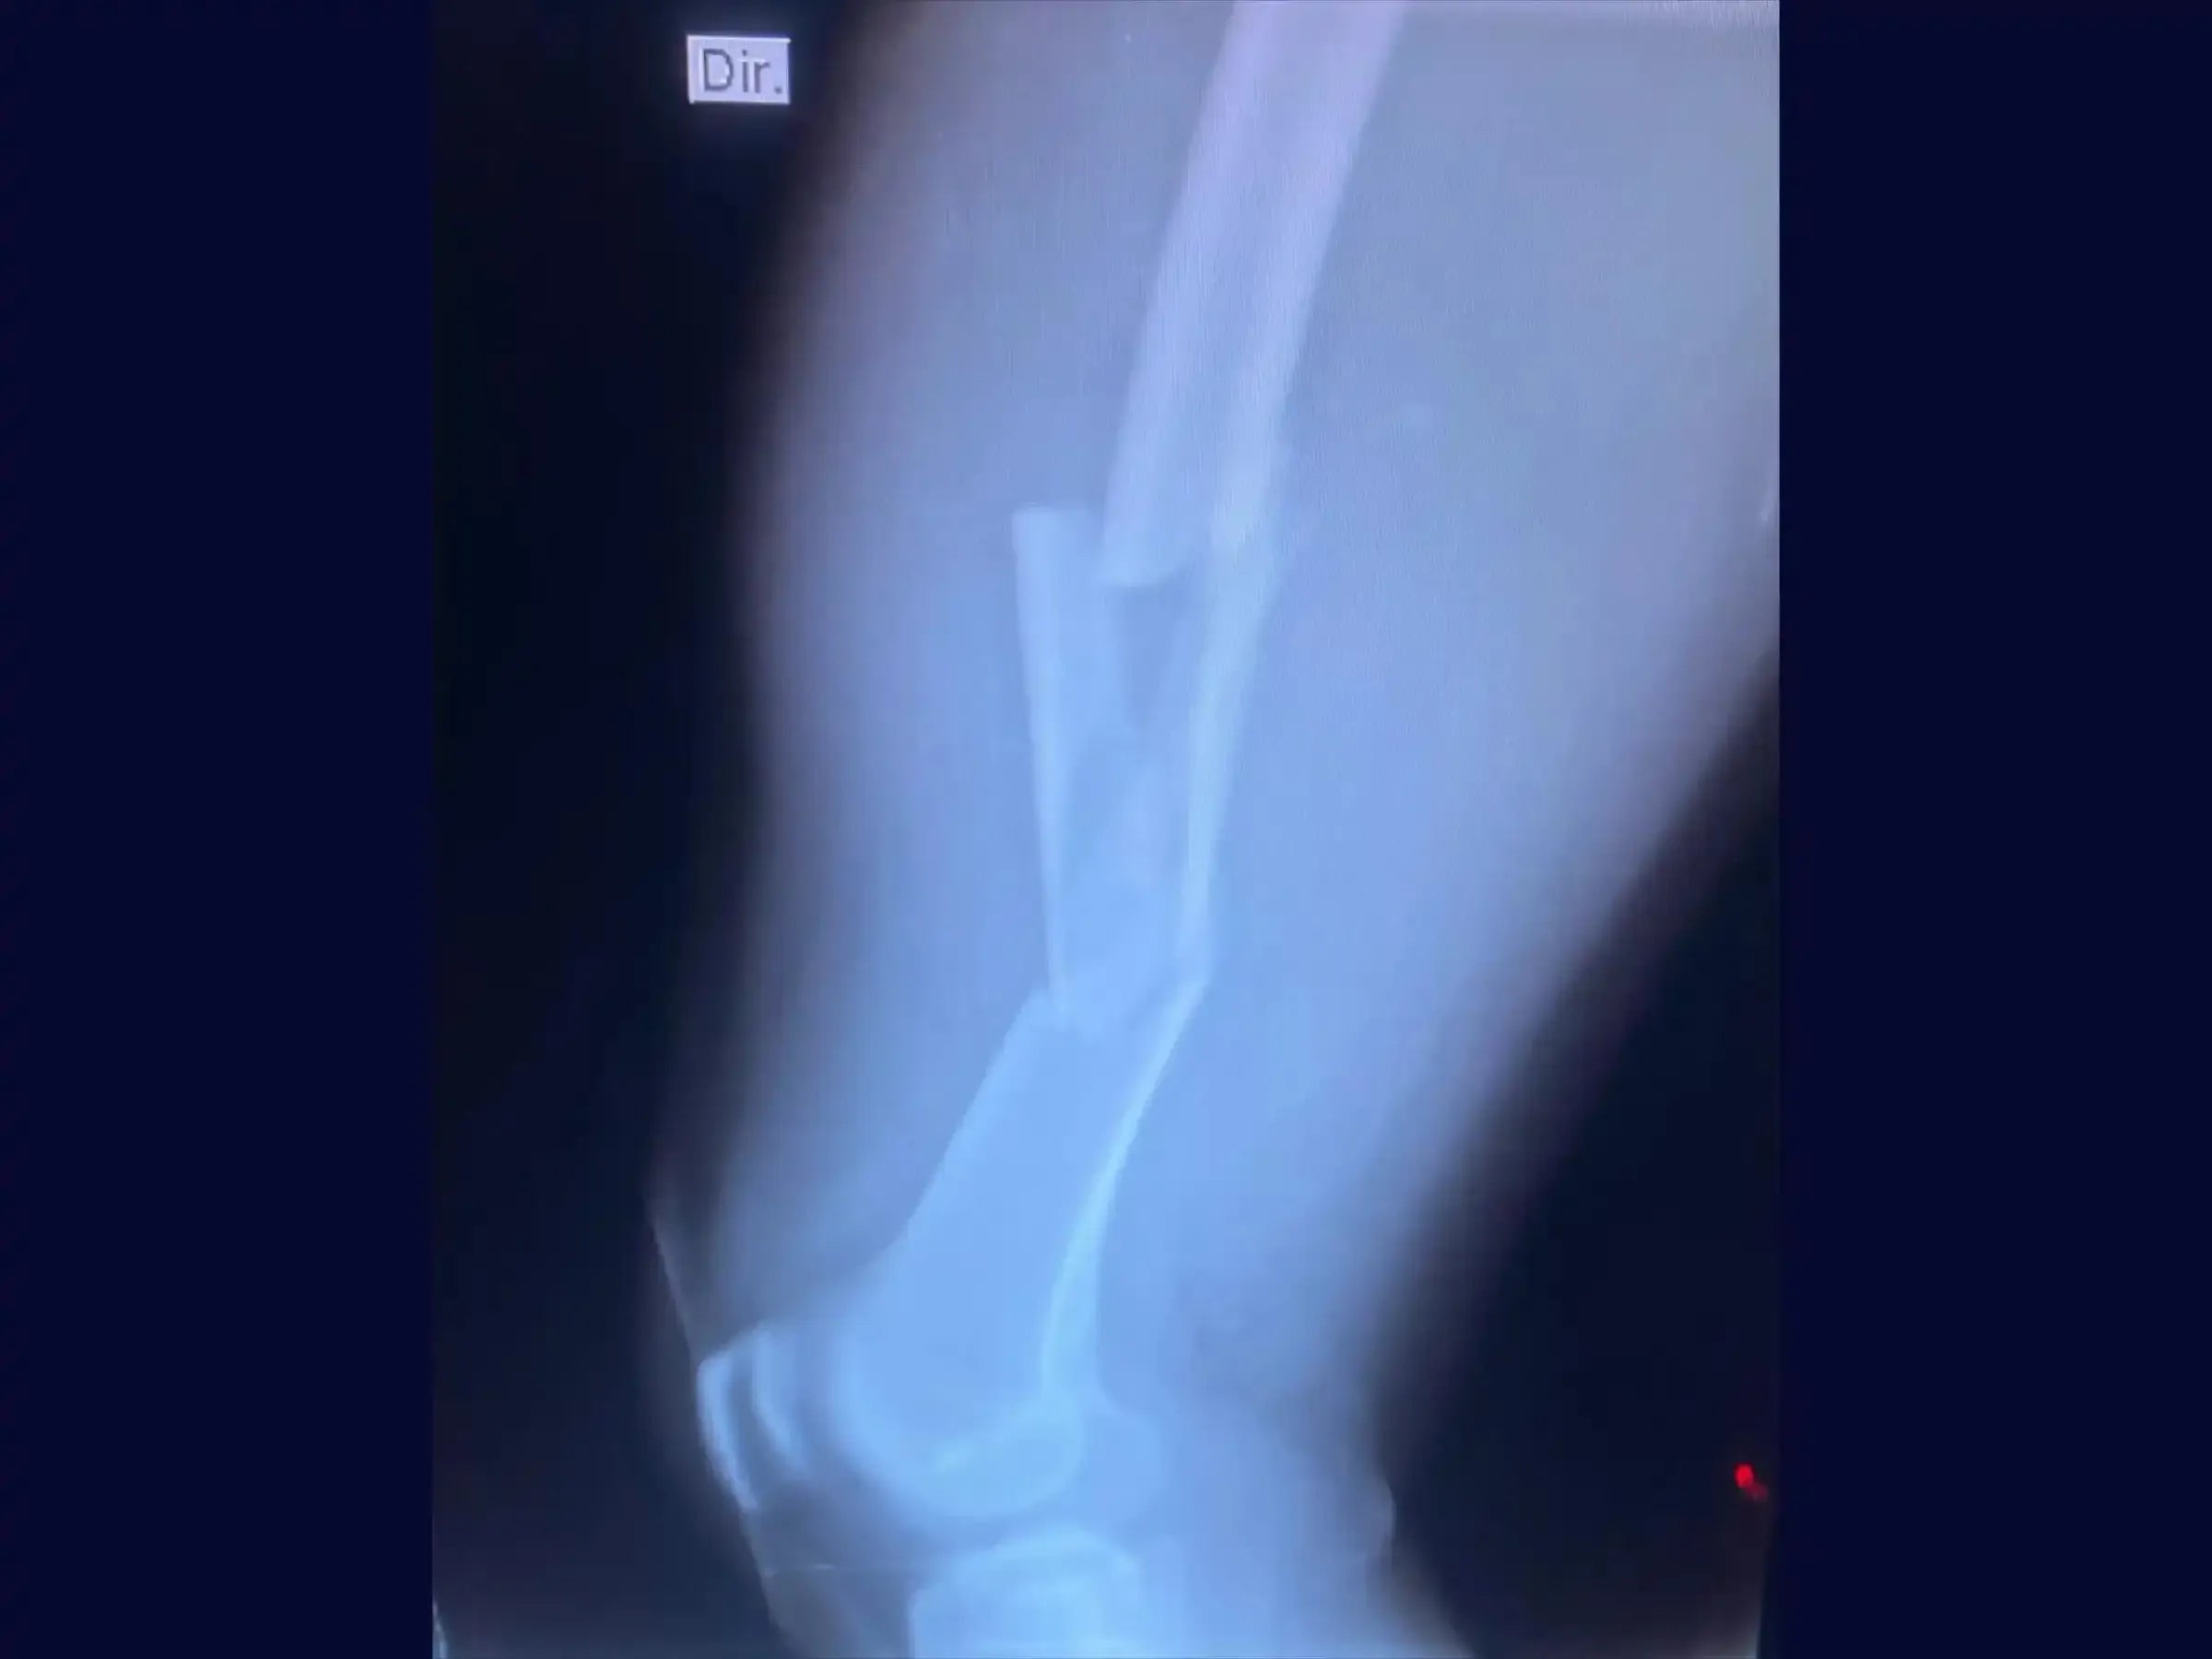

Fratura Diafisária de Fêmur - Haste Intramedular Retrógrada

Aprimore suas habilidades no tratamento de fraturas diafisárias de fêmur em pacientes jovens, frequentemente resultantes de traumas de alta energia. Este treinamento oferece uma imersão técnica no procedimento de fixação com haste intramedular retrógrada, enfatizando o posicionamento adequado do paciente, acessos cirúrgicos precisos e as etapas cruciais para a inserção e bloqueio da haste.

- Tratamento de fraturas diafisárias de fêmur, especialmente em pacientes jovens com trauma de alta energia.